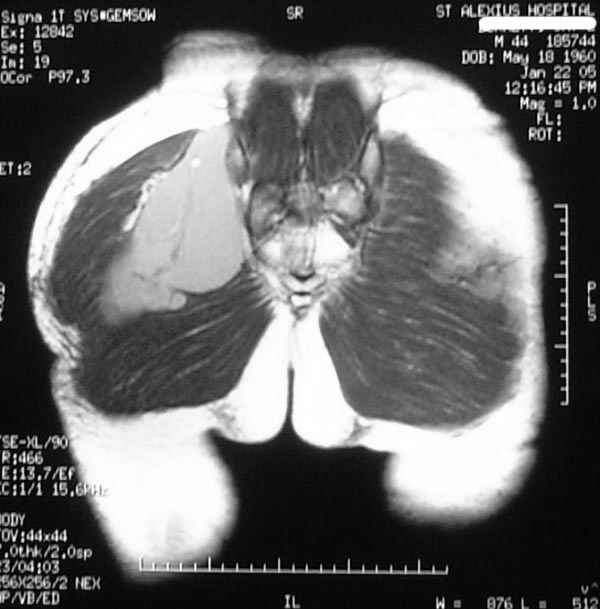

Уважаемые коллеги,Неоднократные пункционные эвакуация (3 раза) крови изягодичной области, после полученной пройзводственнойтравмы (более 1.5 мес) ударом в ягодицу тяжелым, около полутонны предметом.

Рентгенограмма без особенностей, несмещенные переломы лонной и седалищных костей таза.Последная пункция 10 дней назад 180 мл темной крови, после пункции сделано магнито-резонансные исследование (на снимках), какой диагноз и тактика дальнейшего лечения, какие рекомендации?Джолдас Кульджанов

Djoldas Kuldjanov, M.D. 06 Март 2005, 00:25

Разбираемый случай немного отличался от классического Degloving Injury

или Morel-Lavalle Lesion, которые часты при переломах ацетабулума и

костей таза. Состояние, наблюдаемое после удара, в результате чего

образуются обширные полости в тазобедренной области: ягодицы или

большого вертела. Как описал Анатолий, обширные полости заполняются

кровью, затем синовиальной жидкостью, отодвигают сроки операции или

после операции приводят к осложнениям послеоперационных ран.

Описанный случай:

В промежутке около месяца 3 пункции с удалением около 180 мл крови

каждый раз. После исследовании МРТ было принято решение - удаление

гематомы в операционной более широким доступом. Во время операции -

под ягодичной мышцей была капсула, где скопилось около 700 мл

гематомы, после удаления в полости обнаружили несколько закупорившихся

вен и краевой разрыв одной из двух ветвей нижней ягодичной артерии.

После промывания, гемостаза и дренажа, по рекомендации хирурга стенку

полости обработали спреем Tisseel, специальным склерозирующим

препаратом, применяемым пластическими хирургами, затем зашили рану.

Дренажи удалены на 5 день, рана зажила первично. Случай был интересен

применением препарата Tisseel Fibrin Sealant для склерозирования

полостей, только недавно получившим разрешение к применению, хотя по

аннотации в Европе и в Южной Америке применяют давно.